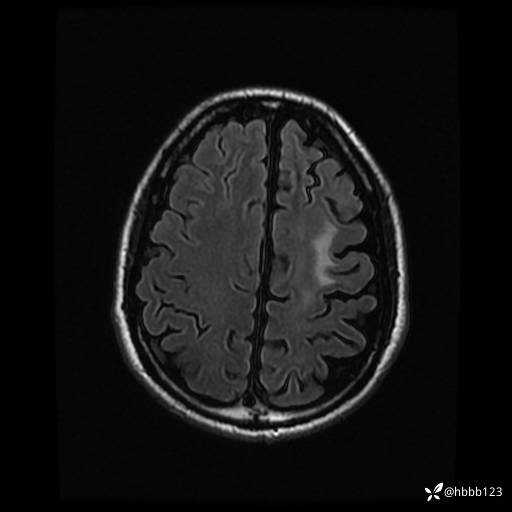

T2 Flair: